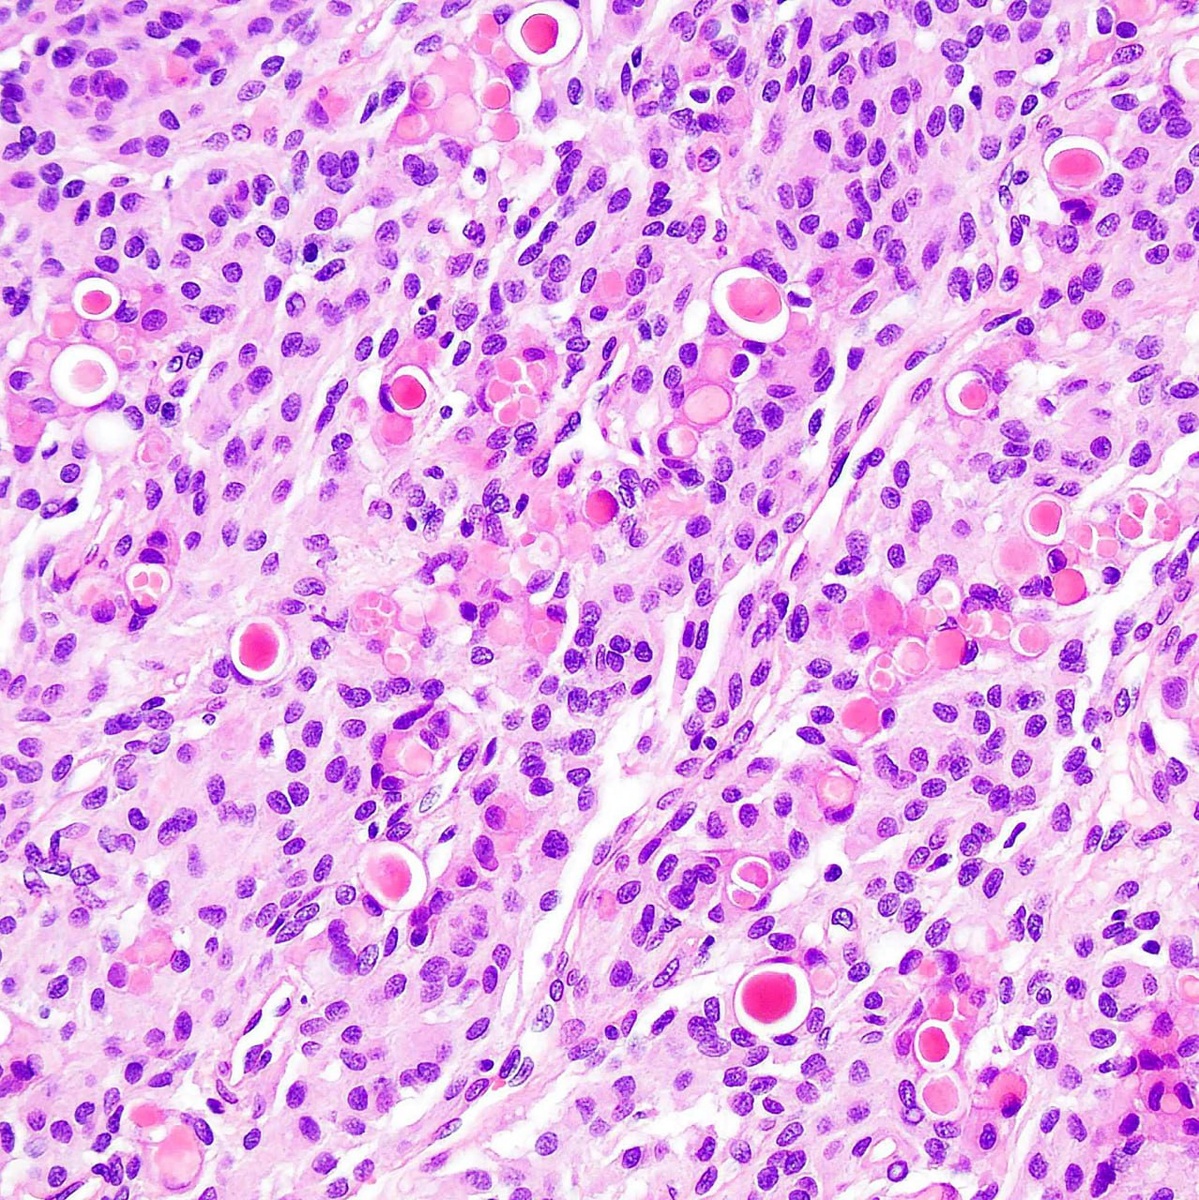

Псаммомные тельца секреторных менингиом положительно окрашиваются PAS и окружены клетками, позитивными к цитокератинам, в зонах псевдожелезистых пространств. Раково-эмбриональный антиген (СЕА) также проявляет положительную реакцию и может выступать в роли серологического маркера для выявления рецидивов. #гистология #менингиома

Псаммомные тельца секреторных менингиом положительно окрашиваются PAS и окружены клетками, позитивными к цитокератинам, в зонах псевдожелезистых пространств.

Раково-эмбриональный антиген (СЕА) также проявляет положительную реакцию и может выступать в роли серологического маркера для выявления рецидивов.